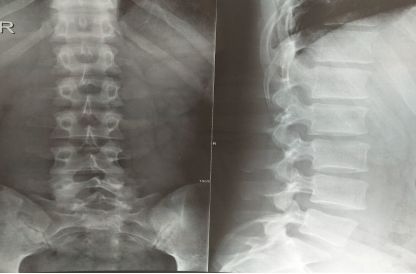

详细了解男士的情况后,我先是诊了他的舌脉,舌红少苔,脉弦细数;又让他去拍了个片子,明确诊断。检查结果,西医诊断:腰椎间盘突出 坐骨神经痛;中医诊断:腰痛(肾阴虚证),治疗上应该采用滋补肾阴,濡养筋脉的治疗原则。